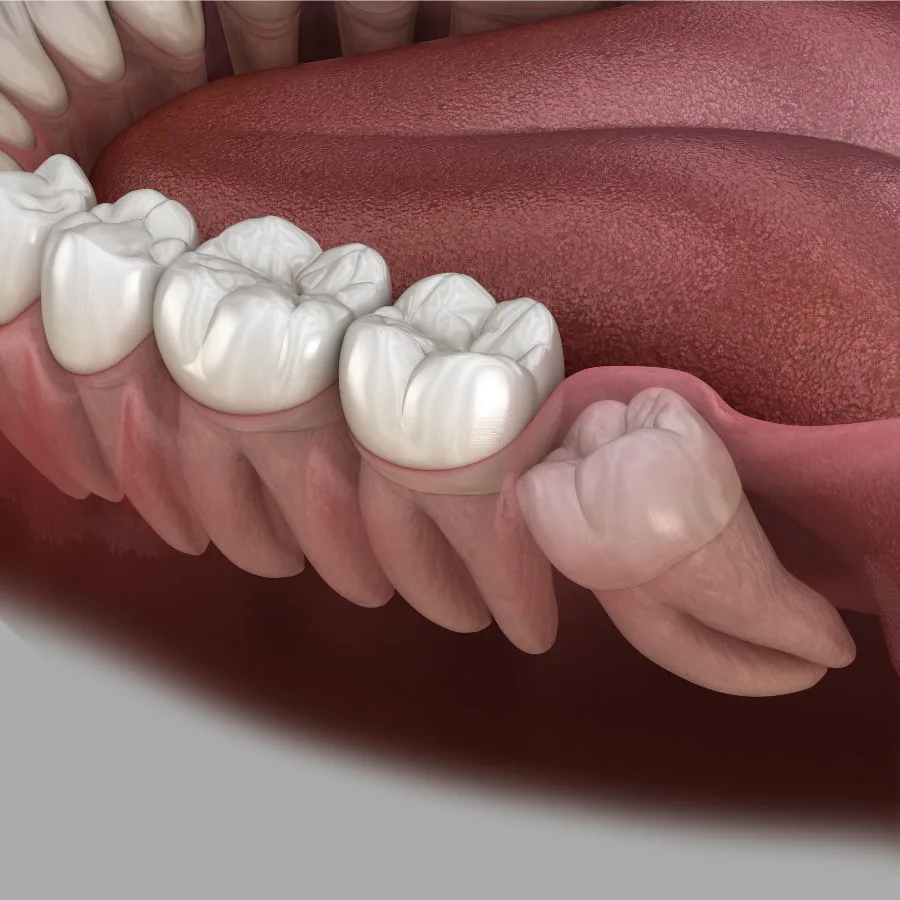

جراحی دندان عقل یکی از رایجترین عملهای دندانپزشکی است که به منظور حذف دندانهای عقل انجام میشود. دندان عقل چیه؟ این دندانها معمولاً در سنین 17 تا 25 سالگی رشد میکنند و در آخرین قسمت فک بالا و پایین قرار دارند. در بسیاری از موارد، دندان عقل به دلیل عدم فضای کافی برای رشد یا رشد نادرست، به مشکلاتی مانند درد، التهاب یا عفونت منجر میشود. برای رفع این مشکلات، جراحی دندان عقل ضروری است. جراح دندان عقل با استفاده از تکنیکهای دقیق و تجهیزات پیشرفته، دندانهای عقل را از فک بیمار خارج کرده و از بروز عوارض جدی جلوگیری میکند. این جراحی معمولاً تحت بیحسی موضعی انجام میشود و در بیشتر موارد، بیماران بعد از عمل به سرعت بهبود مییابند. برای انجام جراحی دندان عقل، مراجعه به یک جراح دندان عقل با تجربه و متخصص ضروری است.

جراحی دندان عقل برای افرادی که دندان عقل آنها به درستی رشد نکرده و باعث ایجاد مشکلاتی مانند درد، عفونت، یا آسیب به دندانهای مجاور میشود، ضروری است. افرادی که دندان عقل آنها به صورت نهفته یا نیمهنهفته در فک باقی میماند، ممکن است با مشکلاتی مانند التهاب لثه، تجمع باکتریها و پوسیدگی مواجه شوند. همچنین کسانی که فضای کافی برای رشد دندان عقل ندارند یا دندانهایشان در موقعیتی نامناسب قرار گرفتهاند، باید برای جراحی دندان عقل اقدام کنند. این جراحی میتواند از مشکلات جدیتری مانند آسیب به ریشه دندانهای مجاور، عفونتهای شدید و دردهای مداوم جلوگیری کند. مشاوره با متخصص کشیدن دندان عقل میتواند به تشخیص دقیق نیاز به جراحی کمک کند.